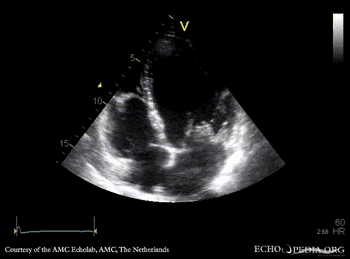

| PLAX: thickend mitral valve leaflets, prolaps of PMVL